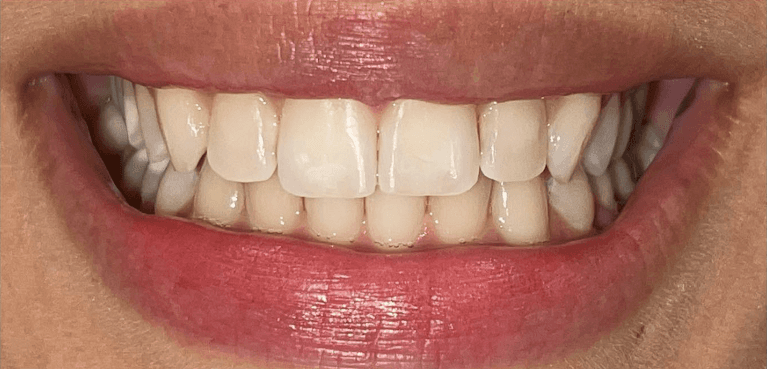

Invisalign Orthodontic treatment completed in 8 months to straighten teeth and improve esthetics.